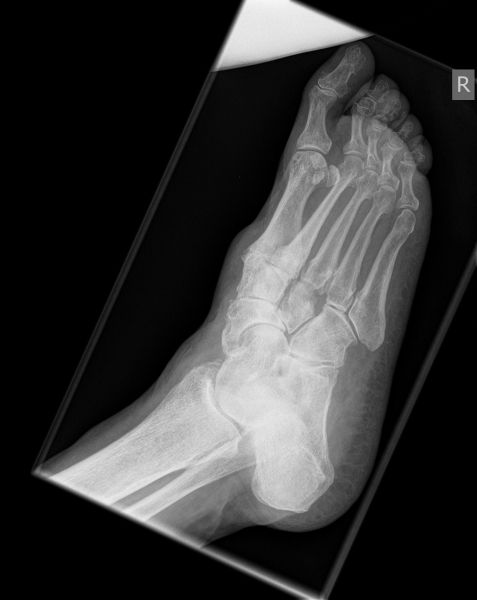

Talonavikular-, navikulocuneiforme- und calcaneocuboidale Arthrosen, also Arthrosen in der Chopart- und Bona-Jäger-Gelenklinie, zeigen sich wesentlich seltener und können in Kombination von Arthrosen aller Gelenke des Mittelfußes auftreten. Die Diagnostik beinhaltet grundsätzlich die ausführliche Untersuchung des gesamten Fußes im Stehen, im Liegen und beim Gehen. Ein Röntgenbild des Fußes im Stehen in zwei Ebenen, ergänzend eine schräge Aufnahme, sowie Saltzman und OSG-Bildgebung sind für die Diagnose und Therapieplanung essentiell. Bei Planung eines operativen Eingriffes sollte eine Computertomographie des gesamten Fußes durchgeführt werden. Zunächst sollte die konservative Therapie mittels Schmerzmedikation, Infiltration, Manueller Therapie, Einlagen, Schuh-Modifikation, Orthesen, orthopädischem Schuhwerk und ggf. eine Strahlentherapie voll ausgeschöpft werden. In zweiter Linie steht die operative Therapie. Chirurgische Eingriffe beinhalten typischer Weise die selektiven Arthrodesen der betroffenen Mittelfußgelenke. Hier wird meist die mediale Säule behandelt, die Arthrodesen der mobileren lateralen Säule sind ein Thema in der Diskussion 2.

Die Diagnostik beinhaltet die komplette klinische Untersuchung des Patienten bei entkleidetem Unterkörper mit Funktionstests, Abtasten der entsprechenden Gelenkreihen (Chopart, Bona Jäger und Lisfranc) und Überprüfung der Beweglichkeit der Tarsometatarsalgelenke mit dem Klaviertasten-Test 11. Beurteilt werden Fußformveränderungen, osteophytäre Anbauten, sowie eine mögliche Verkürzung des M. gastrocnemius-soleus-Komplexes mit Hilfe des Silfverskjöld-Tests 12. Es werdemRöntgenaufnahmen des Fußes im Stehen in 2 Ebenen und ergänzend eine Schrägaufnahme des Fußes durchgeführt. Bei Fußfehlstellungen erfolgt zusätzlich das Röntgen des oberen Sprunggelenks im Stehen und eine Saltzman-Aufnahme 13.